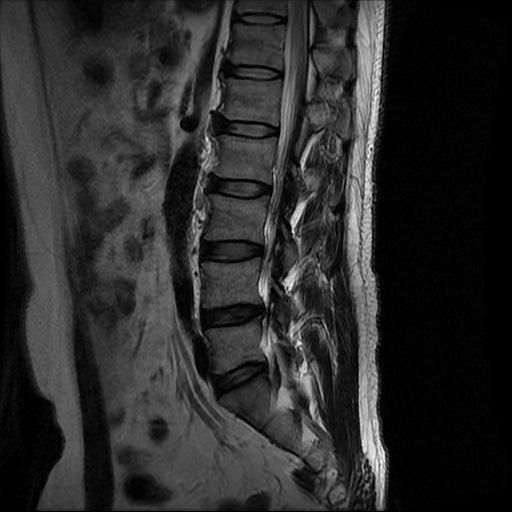

허리 MRI 디스크 상태 분석 부탁드립니다

검진 차 MRI찍었는데 분석 부탁드립니다.

건협에서는 관리해야 된다는데 디스크 협착이나 팽윤 등이 있는 상태인지 궁금합니다.

우선 현재로썬 사진만으론 판단을 하기에 제한이 되지만 사진상 디스크 상태는 심해보이지 않습니다.

요추부위의 하부 에서 약간의 팽윤이나 돌출로 의심해볼수 있는 정도이지만, 정확한 상태는 관련 전문의에게 진료시 문의를 하시는 것을 추천드립니다.